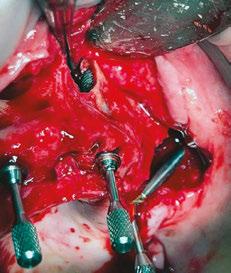

Following the induction of general anesthesia, extraoral and intraoral local anesthesia was applied. To avoid exposing the large subantral bony defects, mini-flaps were elevated at the pterygoid landing areas to expose the hamular notch. The pterygoid fossa was identified via probing, and pterygoid implant placement ensued. Following the PATZi protocol, bilateral pterygoid implants were placed first and both achieved insertion torque between 45+ Ncm.

Following PATZi, anterior support was sought next. As such, the nasal mucosa was elevated to expose the floor of the nasal cavity and the bone of the inferior conchae. A pair of 25 mm transnasal implants were placed, and each achieved high insertion torque of 45+ Ncm (Figures 9-11). Continuing with the PATZi protocol and treatment plan, 42.5 mm long zygomatic implants were placed in both zygomas. The zygomatic implants were placed using an extrasinus approach and both achieved insertion torque of 45+Ncm. Buccal fat pedicles were advanced bilaterally to cover extrasinus portions of the zygomatic implants, and flap closure was achieved with 4-0 chromic gut suture. The patient was immediately temporized with a screw-retained transitional bridge (Figure 12), and a final zirconia restoration was delivered after 8 months of healing (Figure 13).